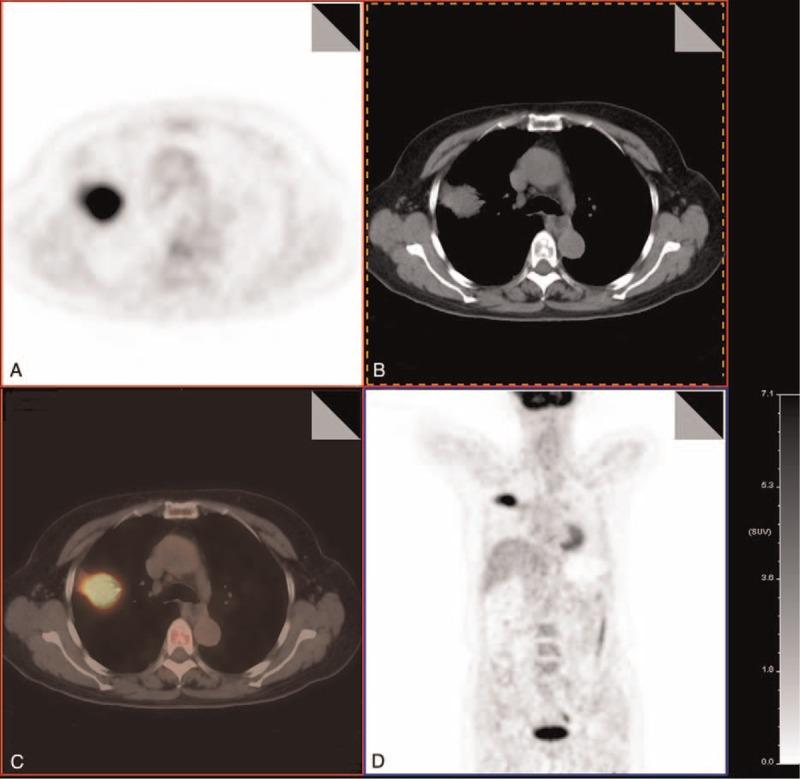

A 62-year-old woman was hospitalized due to a swelling pain located in the right side of her back that persisted for >1 month. Local CT examination indicated a pulmonary infection and anti-infective therapy was administered; however, her symptoms did not improve. In the hospital, a lung CT scan with enhancement showed hyperintensity of the right upper lobe (RUL), ill-defined margins, inhomogeneous density, with air bronchograms, and mild-to-moderate enhancement. PET/CT showed a slight hyperintensity of mass with high uptake (about 14.7 standardized uptake value [SUV]), and no high uptake was found in other locations.

Finally, the PPL-DLBCL manifestation was similar to other types of PPL clinical manifestations and CT manifestations, but the PPL-DLBCL PET/CT showed an apparent, high metabolism. CT-guided percutaneous transthoracic needle biopsy can clearly diagnose the disease.